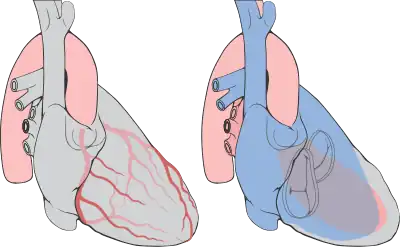

Les artères coronaires, dont le nom vient de leur disposition en couronne autour du cœur, sont des artères recouvrant la surface du cœur, permettant de vasculariser (irriguer), et par conséquent de nourrir, le muscle cardiaque (myocarde). On distingue l'artère coronaire gauche et l'artère coronaire droite, toutes deux prenant naissance de l'aorte.

Artère coronaire gauche

Elle débute par un tronc commun naissant du sinus aortique antéro-gauche, juste au-dessus de la valvule aortique semi-lunaire gauche. Elle passe en arrière du tronc artériel pulmonaire gauche et sous l'auricule gauche qui se divise rapidement en :

- une artère interventriculaire antérieure (ou IVA) qui descend dans le sillon interventriculaire antérieur. Elle donne plusieurs artères septales antérieures, qui pénètrent dans le septum interventriculaire vascularisant les 2/3 supérieurs du septum et notamment les branches du faisceau de His, plusieurs artères diagonales restant à la surface du cœur, en regard du ventricule gauche, et de courts « rameaux droits » vascularisant le ventricule droit. La grande veine du cœur chemine à la gauche de l'IVA ;

- une artère circonflexe, dans le sillon auriculo-ventriculaire postérieur, et qui donne des artères postéro-latérales, appelées également artères marginales, dont l'artère latérale du ventricule gauche, irriguant la paroi postérieure du ventricule gauche et des artères atriales gauches, antéro-supérieures, du bord gauche et postérieure.

Artère coronaire droite

Elle dessine un « C » dans le sillon auriculo-ventriculaire antérieur. On distingue globalement un premier segment horizontal, un deuxième segment vertical et un troisième segment horizontal. Elle se divise à la partie inférieure du cœur en artère interventriculaire postérieure (ou IVP) et en artère rétroventriculaire. La séparation en ces deux dernières s'appelle communément « la croix du cœur ». L'artère coronaire droite irrigue le ventricule droit et la partie inférieure du ventricule gauche.